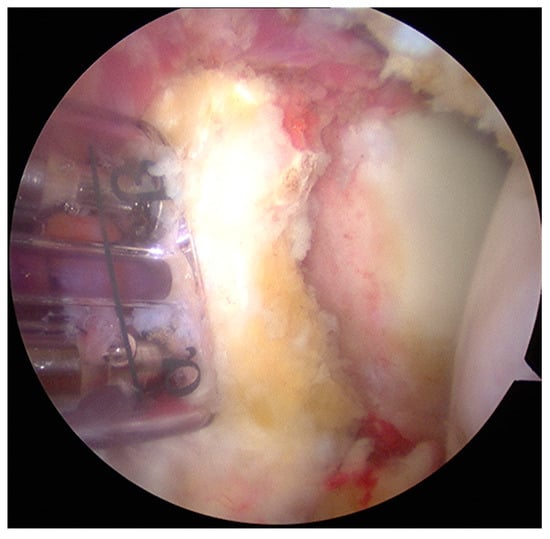

- The graft was positioned on the anterior glenoid neck with the switching stick through the posterior portal (Figure 3).